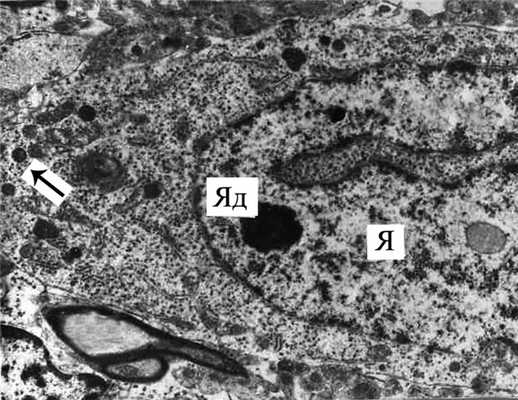

Рис. 5. Пикнотизированный нейрон из СХЯ. Здесь и на рис. 6: Я - ядро. Ув. 3000.